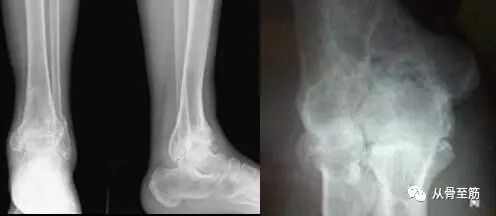

创伤性关节炎,顾名思义是由于外伤引起的以关节软骨的退化变性和继发的软骨增生、骨化为主要病理变化,以关节疼痛、活动功能障碍为主要临床表现的一种疾病。以青壮年和运动员多见。创伤性关节炎多发生于活动频繁或负重的关节,如膝关节、踝关节、肘关节。?

关节扭伤后X光片未显示骨折;或者关节内骨折得到解剖复位,即使X片显示骨折复位并愈合良好,并不意味着关节功能会完全恢复。因为可能同时伴发软骨、半月板、滑膜、韧带、筋膜的损伤,而这些组织在X片上并不显影。

关节畸形(如膝内外翻,踝关节倾斜,肿瘤等)、骨折成角畸形愈合、某些关节活动频繁或经常采取某种特定姿势、重度肥胖或截肢后单侧肢体承重等,均可造成积累性损伤,加重关节面的磨损和破坏。